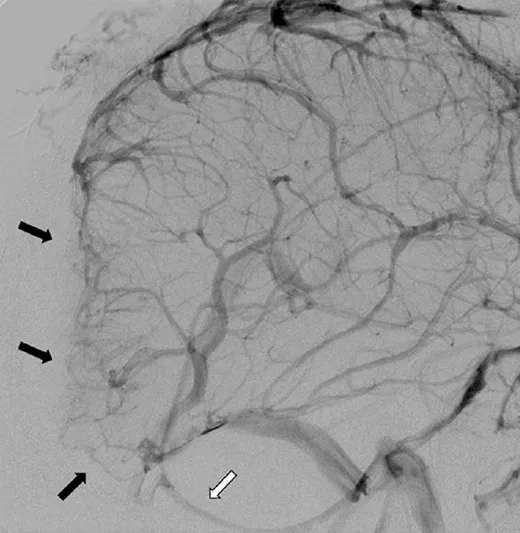

肿瘤经颅骨侵犯至枕部头皮及真皮层。脑血管造影显示上矢状窦、窦汇及横窦近端部分节段血流消失(图2)。深部静脉经枕窦引流(图2),皮质静脉经增粗的Labbe静脉引流(图3)。肿瘤血供丰富,主要动脉供血来自颈外动脉的脑膜支及小脑后下动脉(图4)。术前采用弹簧圈及聚乙烯醇颗粒对颈外动脉的肿瘤供血动脉进行了栓塞治疗(图4)。本病例的鉴别诊断包括血管外皮细胞瘤、脑膜瘤、肉瘤及隐匿性恶性肿瘤。

图2.左侧颈内动脉注射后脑血管造影侧位观。后颅窝/轴外肿瘤侵犯并闭塞了7cm长的上矢状窦后部、窦汇及横窦近端(黑色箭头)。横窦远端可见血流重建。深部静脉经连接直窦与左侧颈静脉球的枕窦引流(白色箭头)